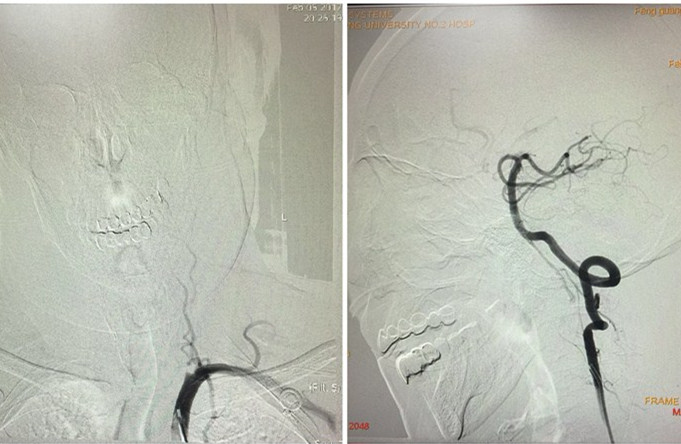

左侧椎动脉闭塞,基底动脉未显影 取栓后通畅的血管

2017年2月5日夜间,当人们还沉浸在春节的热闹气氛中欢度周末时,一位65岁的男性,以“头晕、呕吐1天,意识不清5小时”被送到我院急诊科,患者处于昏迷状态,四肢不能活动、心率快、高热,头颅CT提示脑干、小脑梗死,生命危在旦夕。神经内科住院总医师任宏伟会诊,并请示二线值班姚丽主治医师后,考虑很可能是脑后部重要的血管—椎-基底动脉系统血栓引起血管闭塞。经向家属详细谈明急诊行脑血管造影的必要性后,家属同意了行脑血管造影手术进一步确诊病情,必要时进行取栓手术。科室主任张桂连教授立即组织介入组展淑琴教授、王虎清副教授、高震医师及赵菊凤护师,以最快速度紧张有序地实施脑动脉造影术,造影结果证实了临床诊断,确为左侧椎动脉起始部夹层闭塞,基底动脉内大量血栓,右侧椎动脉纤细。由于基底动脉闭塞预后极差,如果血管不能恢复血流,患者九死一生,因此,患者有立即行支架取栓的必要。经家属同意后,紧张有序的手术在进行中,一次性成功取出长达7cm血栓,取栓后左侧椎动脉及基底动脉显影良好,患者生命体征趋于平稳。所有在场的手术人员,虽然累但都感到很欣慰。